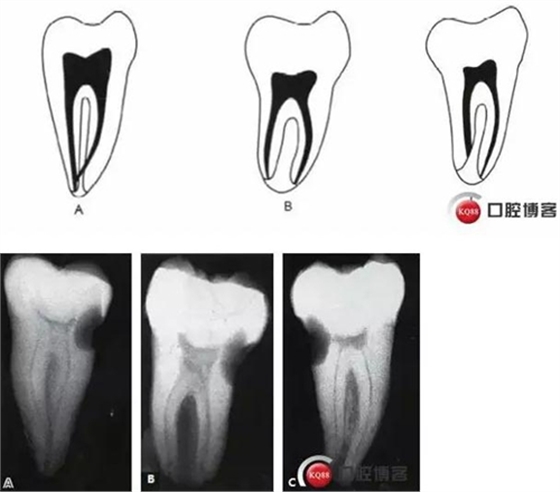

傳統(tǒng)的Melton C形根管分類法雖深化了對根管結(jié)構(gòu)的認(rèn)識,但由于是基于組織學(xué)的分類,不能指導(dǎo)臨床實(shí)踐。有學(xué)者基于C形根管X 線特征,結(jié)合顯微CT掃描結(jié)果,提出了一種新的分類方法,便于臨床應(yīng)用。

這種分類方法將下頜第二磨牙分為3 型:

I型:融合型,X線片上見2個(gè)根管,但在根尖區(qū)融合。

II型:分離型,X線片見2個(gè)根管且互相獨(dú)立。

III型:不對稱型,X線片上雖有2個(gè)根管互相獨(dú)立,但一長一短,互不對稱。